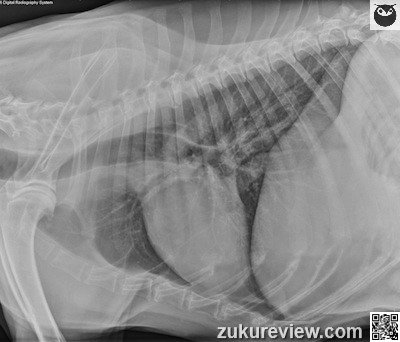

An 11-year-old spayed female German shepherd is presented for pelvic limb weakness.

These are normal thoracic radiographs. There is a small amount of air in the thoracic esophagus dorsal to the carina. This is normal and usually transient.

There is moderate degenerative joint disease of the scapulohumeral joints as well as mild ventral spondylosis at multiple sites of the thoracic and thoracolumbar spine.